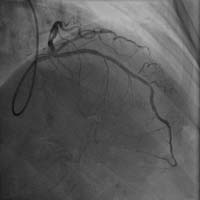

前降支近端嚴重狹窄 介入術后狹窄消失